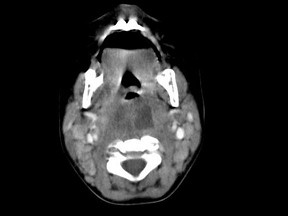

10个月大的婴儿,发热,曾患中耳炎,CT扫描如图所示,正确的描述或诊断是()

A.咽后壁软组织肿胀

B.其内密度不均

C.颈椎骨质未见明显异常

D.咽后壁脓肿

E.咽后壁寒性脓肿

[多选题]10个月大的婴儿,发热,曾患中耳炎,CT扫描如图所示,正确的描述或诊断是()A.咽后壁软组织肿胀B.其内密度不均C.颈椎骨质未见明显异常D.咽后壁脓肿

[多选题] 10个月大的婴儿,发热,曾患中耳炎,CT扫描如图所示,正确的描述或诊断是()A .咽后壁软组织肿胀B .其内密度不均C .颈椎骨质未见明显异常D .咽后壁脓肿E .咽后壁寒性脓肿

[多选题] 10个月大的婴儿,发热,曾患中耳炎,CT扫描如图所示,正确的描述或诊断是()A . 咽后壁软组织肿胀B . 其内密度不均C . 颈椎骨质未见明显异常D . 咽后壁脓肿E . 咽后壁寒性脓肿